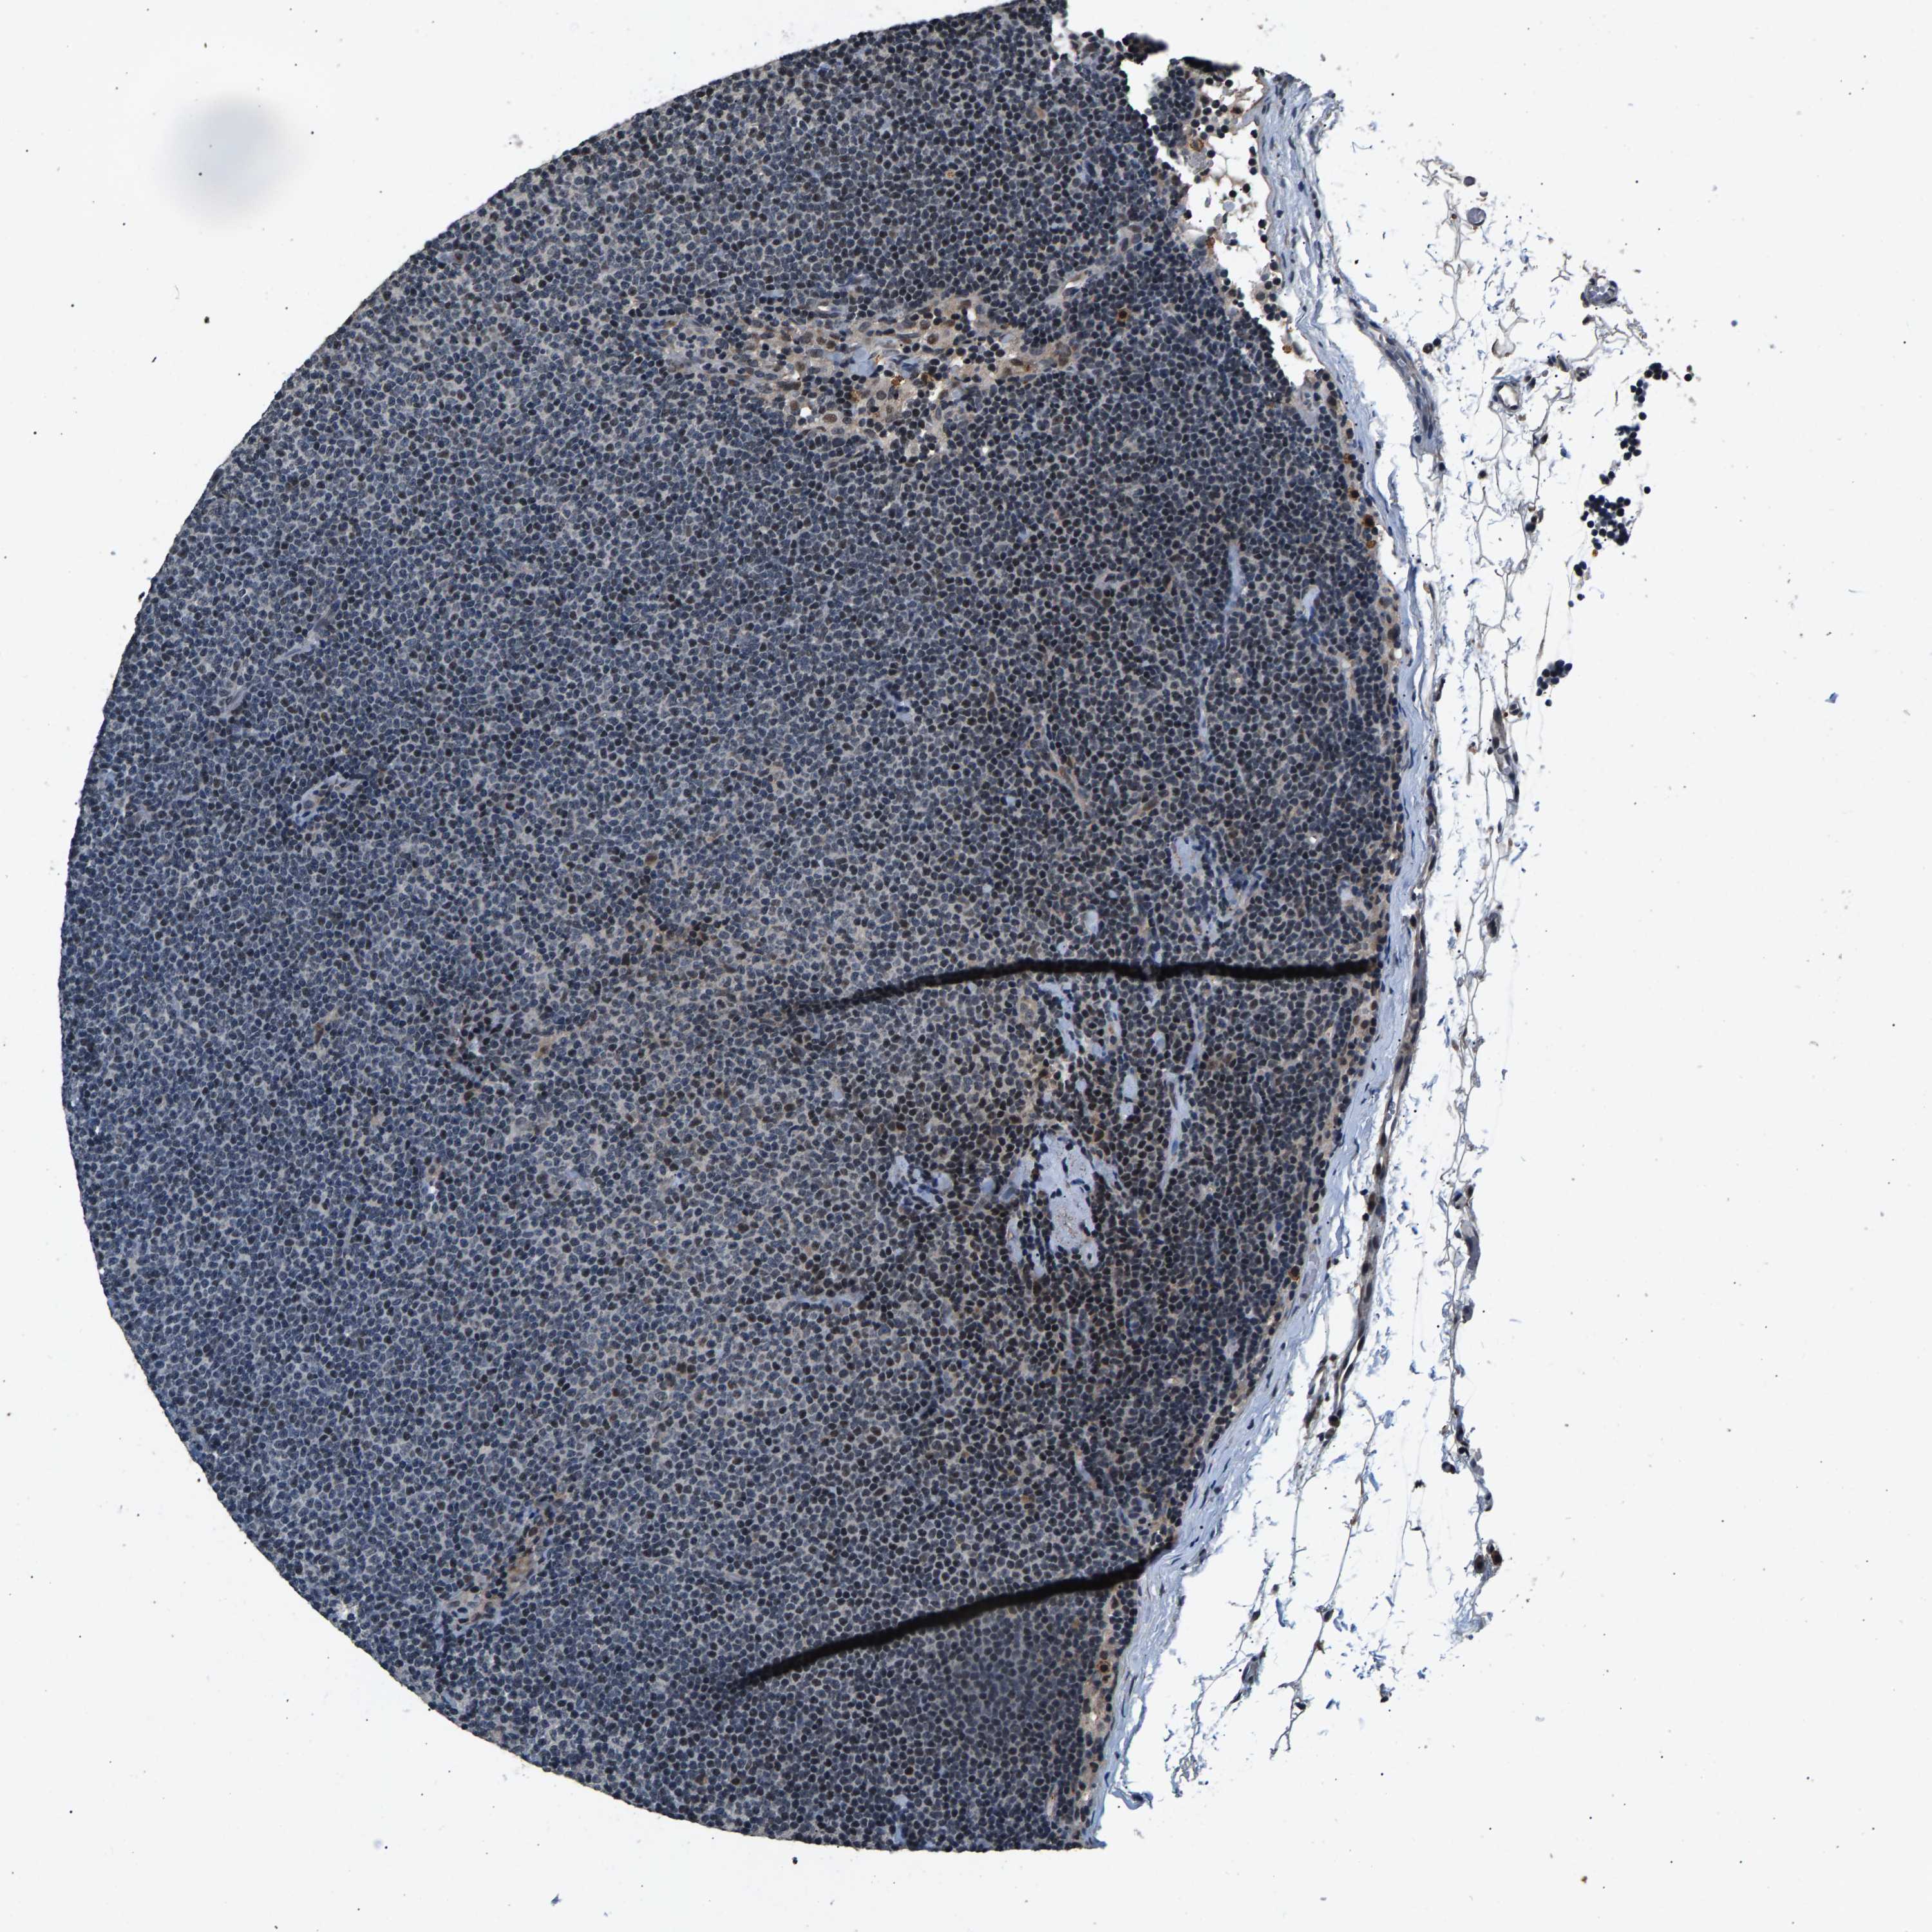

LYMPHOMA - Protein expressioni

A mouse-over function shows sample information and annotation data. Click on an image to view it in a full screen mode. Samples can be filtered based on level of antibody staining by selecting one or several of the following categories: high, medium, low and not detected. The assay and annotation is described here.

Each image is clickable and will lead to virtual microscopy that enables deeper exploration of all samples and also displays staining intensity scores, fraction scores and subcellular localization as well as patient and tissue information for each sample.

Antibody HPA021768

Hodgkin's disease, NOS

Malignant lymphoma, non-Hodgkin's type, High grade

Malignant lymphoma, non-Hodgkin's type, Low grade